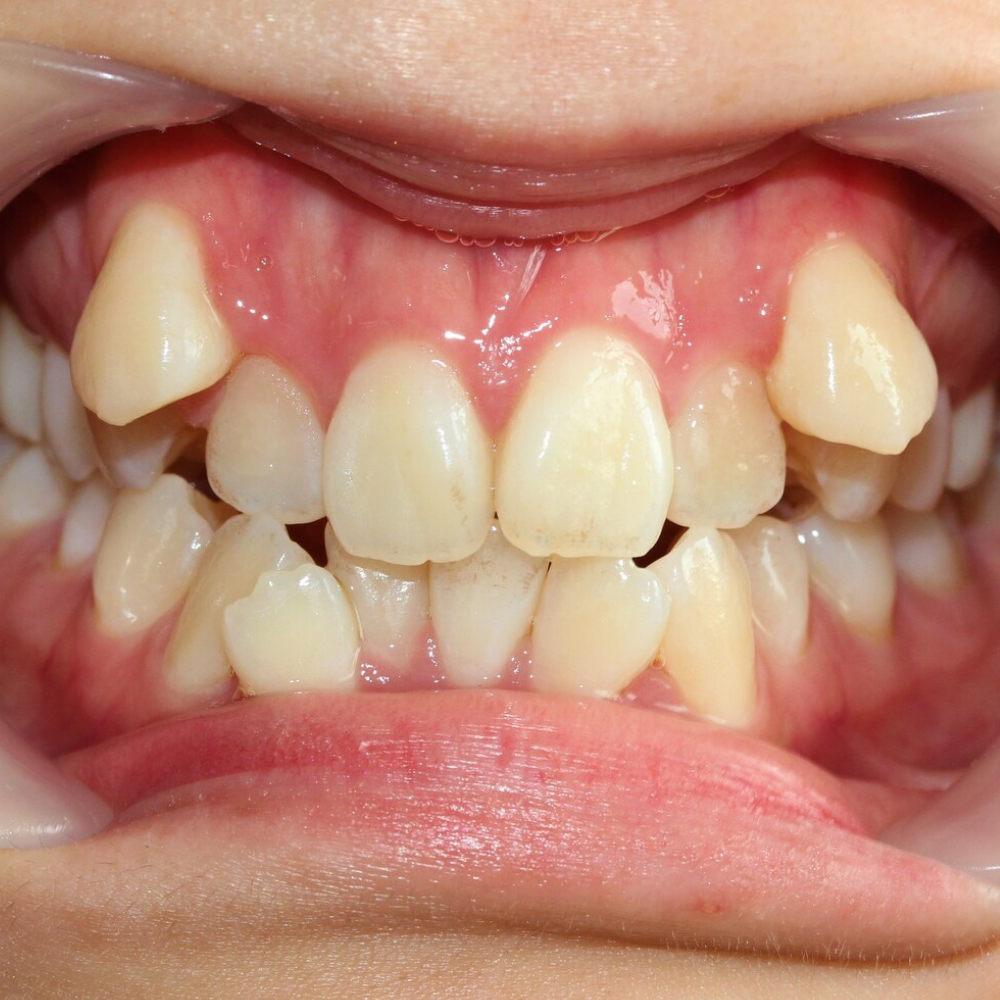

八重歯とは?

八重歯とは犬歯(前から3番目の糸切り歯)が出っ張っている症状。

多くの場合、八重歯だけでなく、出っ歯や口ゴボ、叢生(ガタガタ)を併発しています。

小顔あごが小さい方は、歯がきれいに並ぶスペースが足りません。

犬歯(前から3番目の糸切り歯)は、前歯と奥歯の間に生えてきますが、生える順番最後の方です。

あごが小さくてスペースが足りない場合、先に生えてきた前歯と奥歯がスペースを使い切ってしまいます。

その結果、後から生えてきた犬歯は入る隙間がなく、やむなく歯列の外側から生えてくるしかありません。これが八重歯の正体です。

つまり本来は美人の条件である小顔のせいで、歯並びが悪くなってしまったという状況。